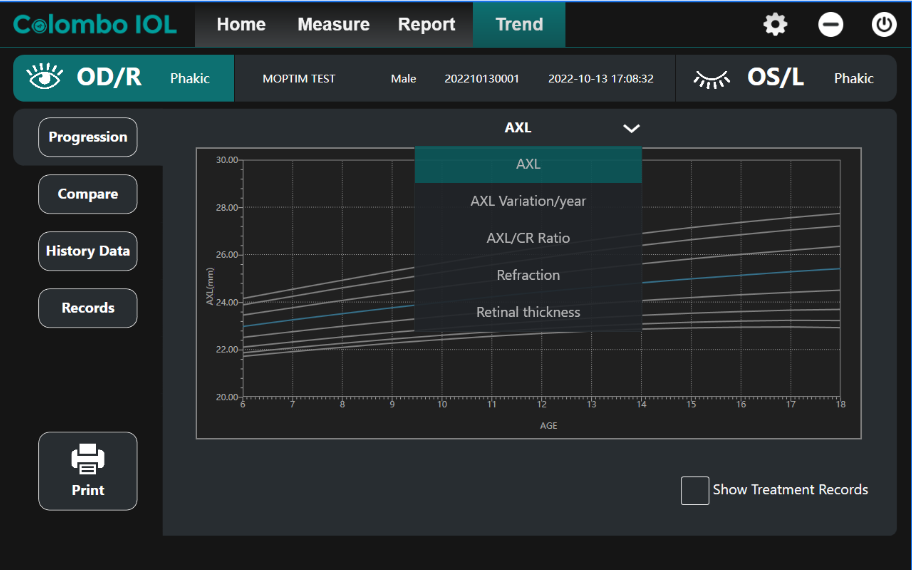

Аналіз прогресії міопії

Colombo IOL надає розширений аналіз трендів міопії, включаючи довжину вісі, варіацію AXL та співвідношення AXL/CR. Використання адаптованих кривих росту для дітей шкільного віку спрощує інтерпретацію даних і підвищує ефективність консультування.